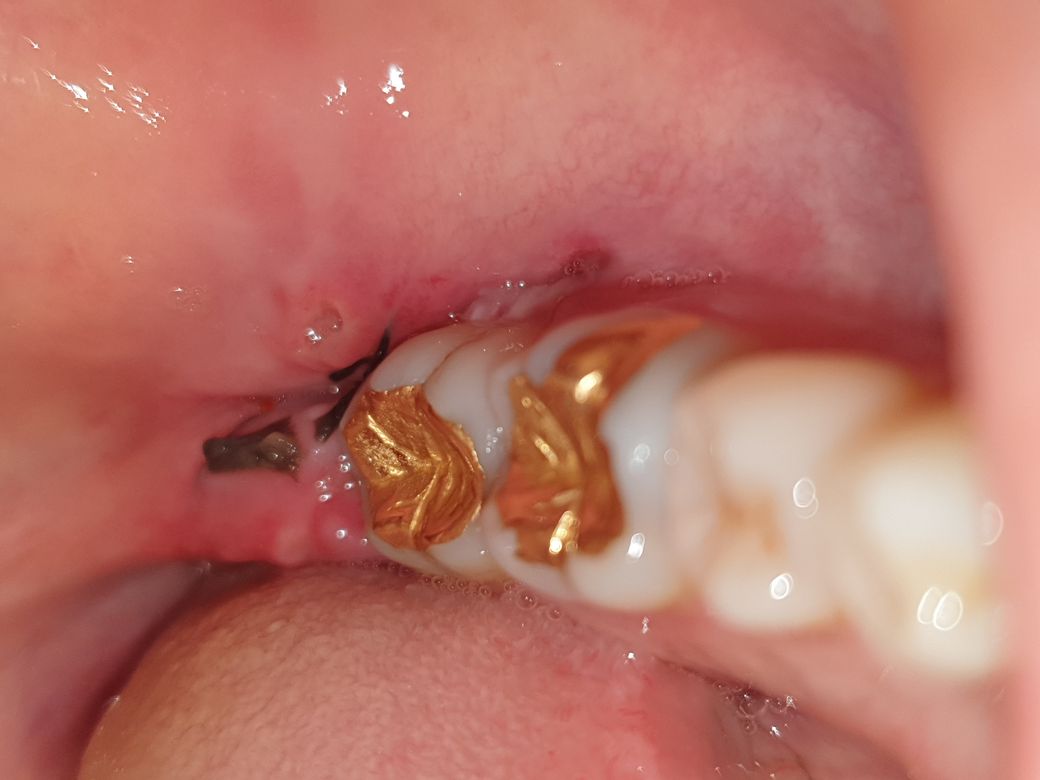

매복사랑니 발치 후 (사진주의) 상태문의

월요일 저녁에 매복 사랑니를 발치하였습니다.

3. 그리고 붓기가 좀 빠지고 나서 보이는게 사랑니 바로 앞쪽 치아 아래 잇몸쪽에도 절개를 한거처럼 보이는데

이쪽 흰색부분은 사랑니 뽑은곳 앞인데 절개를 해서 살이 오르는건가요? ㅠㅠ

• 2번 째 사진

사랑니앞쪽치아의 잇몸도 절개를 하게되는데, 낫는 과정인 것으로 보입니다.

앞쪽 부위 역시 이물질 또는 잇몸 염증이 있어보여 정확한 판단은 어렵습니다.